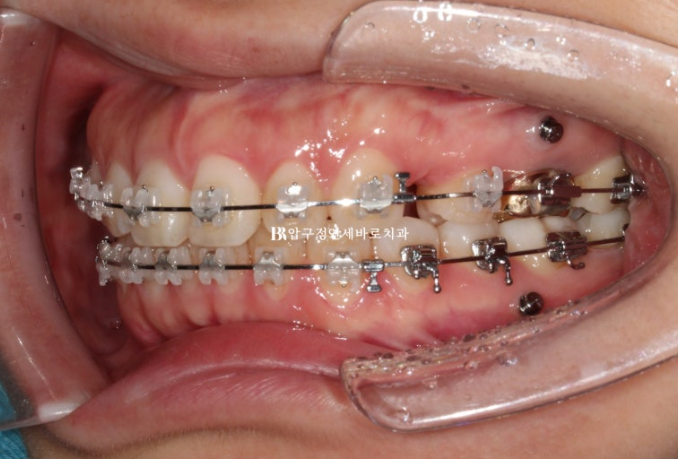

23.11

The procedure was carried out after placing mini-screws.

24.03

About half of the extraction space remained at this point.